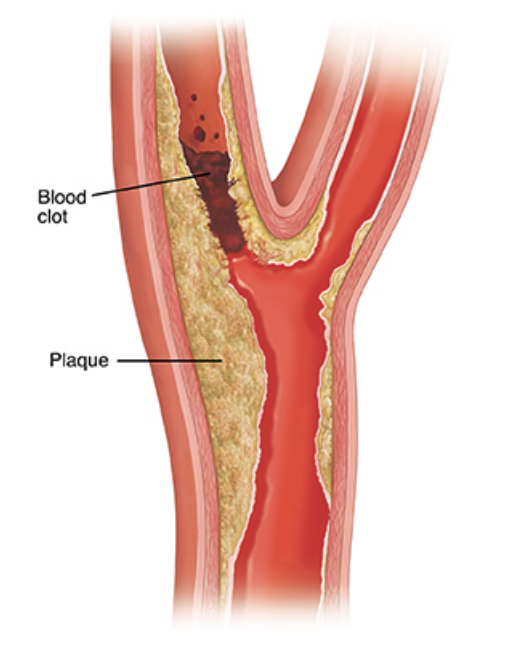

Stroke

What is Hemorrhagic Stroke? (click here)

What is a Thalamic Stroke? (click here)

Blood Pressure and Stroke Link (click here)